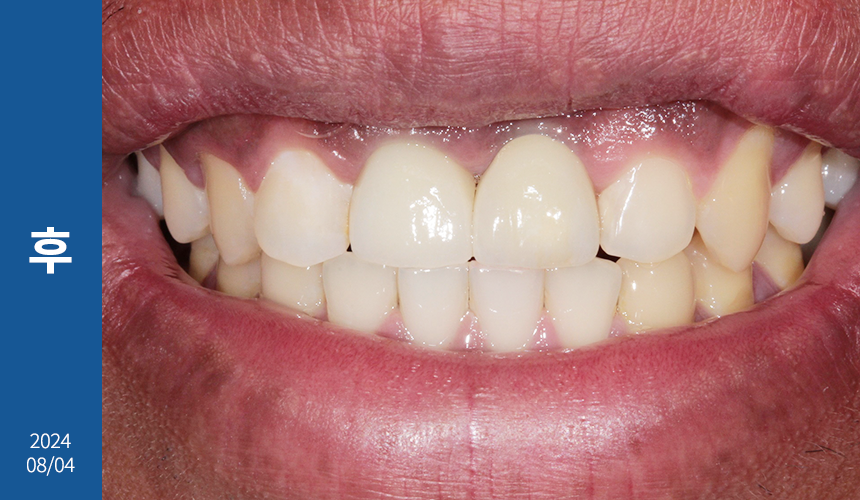

저작 활동이 수월하도록 좌측 인공치 완성 후

우측 임플란트 식립을 진행해 드렸으며

교합도 꼼꼼히 체크해서

안정적인 생활이 가능하게 해드렸답니다.

한 달 후 치근단 사진을 찍어보니

주위 염증 없이 이식된 자리에

잘 위치하고 있었습니다.

오늘은 앞니 임플란트 식립 증례를

소개해 드렸는데요.